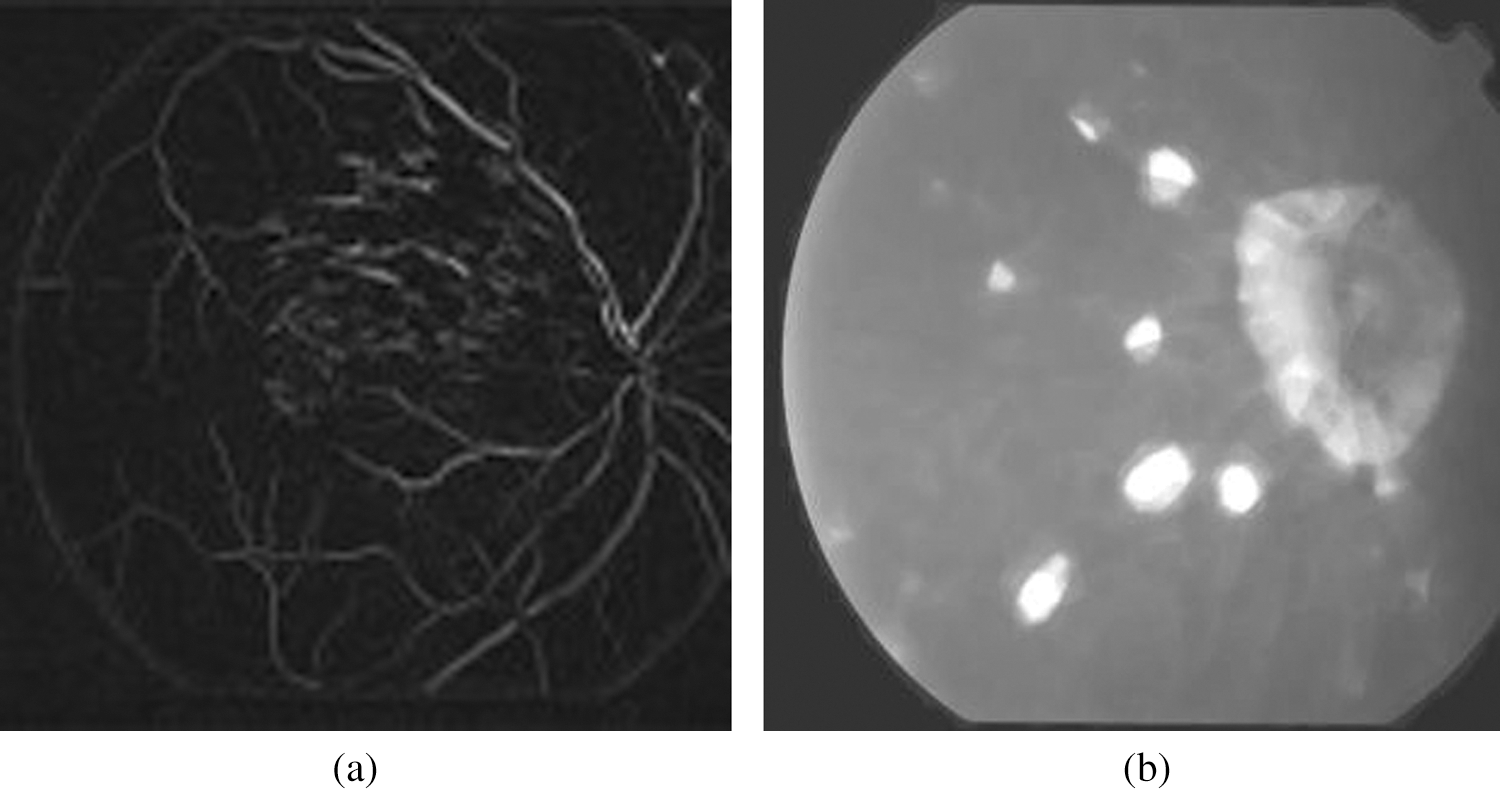

Fig. 5 showed blood vasculature and non-blood vessels. Using morphological filter blood vessels are extracted so as to identify the exudates more efficiently. Using contourlet type of transform the morphological segmentation is performed. Following the classification, validation is performed to identify the results of diagnosis into two classes where first includes Healthy eyes and second includes exudates lesion.

Figure 5: a) Blood vasculature b) Non blood vessels